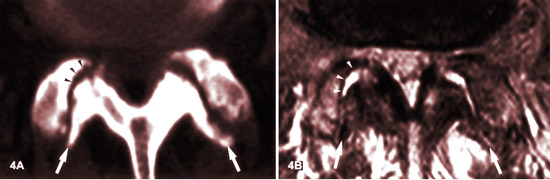

STÉNOSE FORAMINALE DE GRADE 3 ET 4 | CT SCAN LOMBAIRE

Nous évaluons que la sténose foraminale à droite est de grade 3, et à gauche de grade 4.

ARTHROSE FACETTAIRE (spondylarthrose) ET SON APPARENCE IRM :

LES STADES

Source: MR imaging and CT in osteoarthritis of the lumbar facet joints.